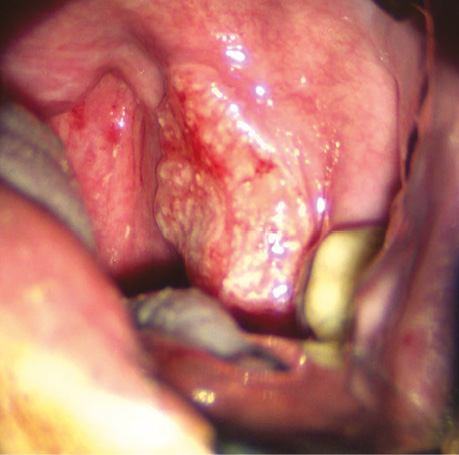

Клінічний випадок № 4

Пацієнт С., 47 років. Плоскоклітинна ВПЛ-асоційована карцинома передньої піднебінної дужки зліва з поширенням на піднебінний мигдалик та уздовж глотково-язикової складки, стадія T2N0M0. Виконано трансоральну CO₂-лазерну резекцію бічної стінки ротоглотки, кореня язика. На рис. 10–13 наведено основні етапи хірургічного втручання.

Рис. 10. Інфільтративне пухлинне ураження передньої піднебінної дужки з поширенням на піднебінний мигдалик та уздовж глотково-язикової складки

Рис. 11. СО2-лазером проводиться розсічення підслизового шару ротоглотки для візуалізації сполучнотканинної капсули піднебінного мигдалика

Рис. 12. СО2-лазером проводиться резекція кореня язика

Рис. 13. Вид операційної рани. Представлено ранову поверхню після трансоральної СО2-лазерної резекції бічної стінки ротоглотки та кореня язика, з чіткою візуалізацією глибини дефекту та анатомічних структур бічної стінки ротоглотки